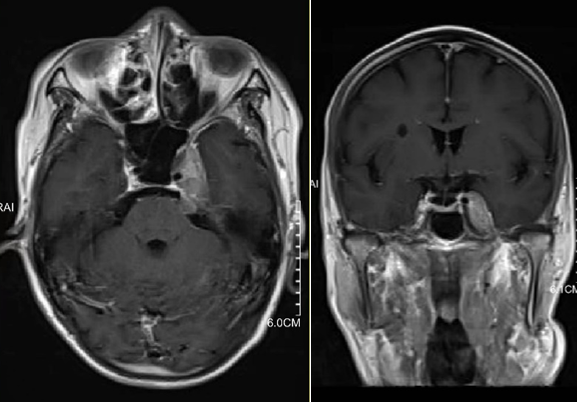

患者,男,72岁。2023年7月因“左面部麻木1月余”检查发现左侧海绵窦肿瘤并向后颅窝生长(图1),当时其他医师手术切除了后颅窝小部分肿瘤(图2),术后病理:脑膜瘤,WHO I级。